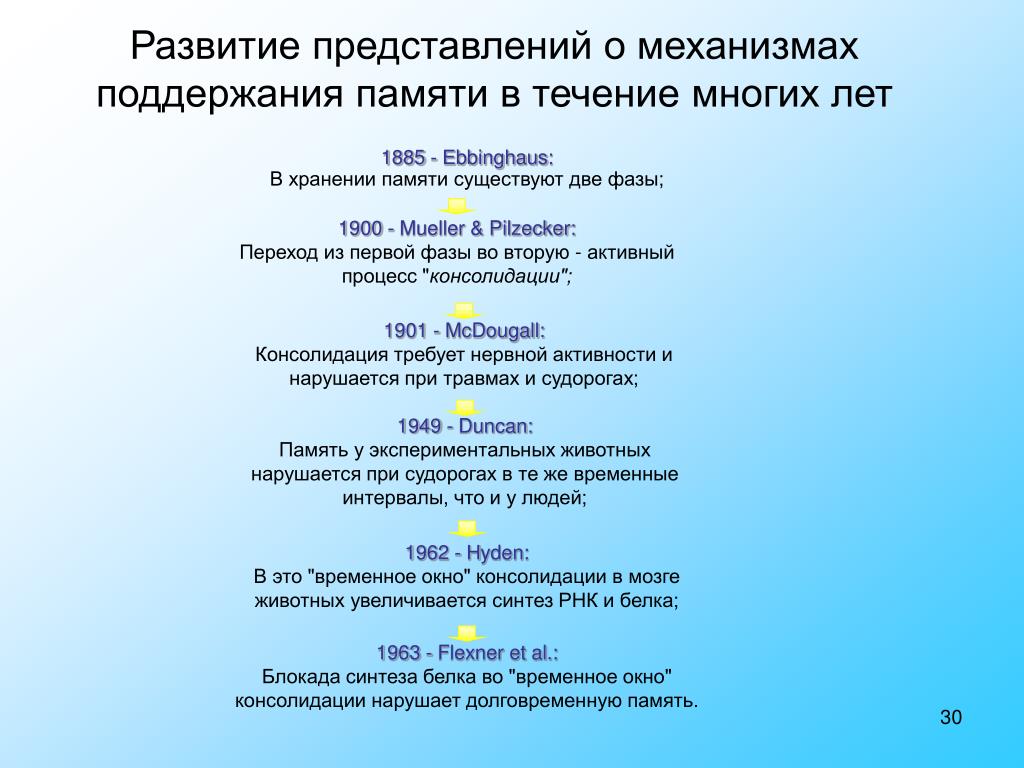

Физиология памяти: Механизмы и исследования